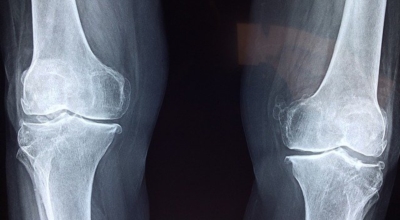

보스웰리아 효능 - 관절 및 연골 건강

많이 함유되어있는 보스웰릭산 성분은 염증을 억제하고 체내 연골 세포의 강화를 통해 초기 관절염, 퇴행성 관절염에 좋아요. 또한 허리디스크 통증, 무릎 연골의 통증을 줄여주고 예방하는 데에도 효과가 있습니다. 시중에 판매되는 보스웰리아 제품들은 모두 이런 관절 및 연골 건강에 집중되어 있는데요 그만큼 보스웰리아는 관절에 좋은 성분이 뛰어난 건강식품이라고 볼 수 있다고 합니다. 실제 한 연구결과에 근거하면 관절염 환자 대상 보스웰리아를 8주간 섭취시 통증이 줄이며 무릎 붓기도 줄어들었다고 합니다.